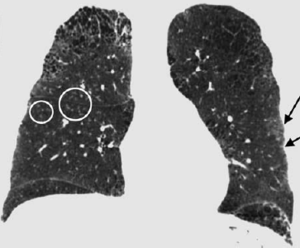

The Impact of Diffusion-Weighted MRI on the Definition of Gross Tumor Volume in Radiotherapy of Non-Small-Cell Lung Cancer

Publication: PLoS One. 2016 Sep 9;11(9):e0162816. PMID: 27612171 | PDF Authors: Fleckenstein J, Jelden M, Kremp S, Jagoda P, Stroeder J, Khreish F, Ezziddin S, Buecker A, Rübe C, Schneider GK. Institution: Department of Radiotherapy and Radiation Oncology, Saarland University Medical Center, Homburg, Germany. Background/Purpose: The study was designed to evaluate diffusion-weighted magnetic resonance imaging (DWI) vs. PET-CT of the thorax in the determination of gross tumor volume (GTV) in radiotherapy planning of non-small-cell lung cancer (NSCLC). MATERIALS AND METHODS: Eligible patients with NSCLC who were supposed to receive definitive radio(chemo)therapy were prospectively recruited. For MRI, a respiratory gated T2-weighted sequence in axial orientation and non-gated DWI (b = 0, 800, 1,400 and apparent diffusion coefficient map [ADC]) were acquired on a 1.5 Tesla scanner. Primary tumors were delineated on FDG-PET/CT (stGTV) and DWI images (dwGTV). The definition of stGTV was based on the CT and visually adapted to the FDG-PET component if indicated (e.g., in atelectasis). For DWI, dwGTV was visually determined and adjusted for anatomical plausibility on T2w sequences. Beside a statistical comparison of stGTV and dwGTB, spatial agreement was determined with the "Hausdorff-Distance" (HD) and the "Dice Similarity Coefficient" (DSC). RESULTS: Fifteen patients (one patient with two synchronous NSCLC) were evaluated. For 16 primary tumors with UICC stages I (n = 4), II (n = 3), IIIA (n = 2) and IIIB (n = 7) mean values for dwGTV were significantly larger than those of stGTV (76.6 ± 84.5 ml vs. 66.6 ± 75.2 ml, p<0.01). The correlation of stGTV and dwGTV was highly significant (r = 0.995, p<0.001). Yet, some considerable volume deviations between these two methods were observed (median 27.5%, range 0.4-52.1%). An acceptable agreement between dwGTV and stGTV regarding the spatial extent of primary tumors was found (average HD: 2.25 ± 0.7 mm; DC 0.68 ± 0.09). CONCLUSION: The overall level of agreement between PET-CT and MRI based GTV definition is acceptable. Tumor volumes may differ considerably in single cases. DWI-derived GTVs are significantly, yet modestly, larger than their PET-CT based counterparts. Prospective studies to assess the safety and efficacy of DWI-based radiotherapy planning in NSCLC are warranted. |